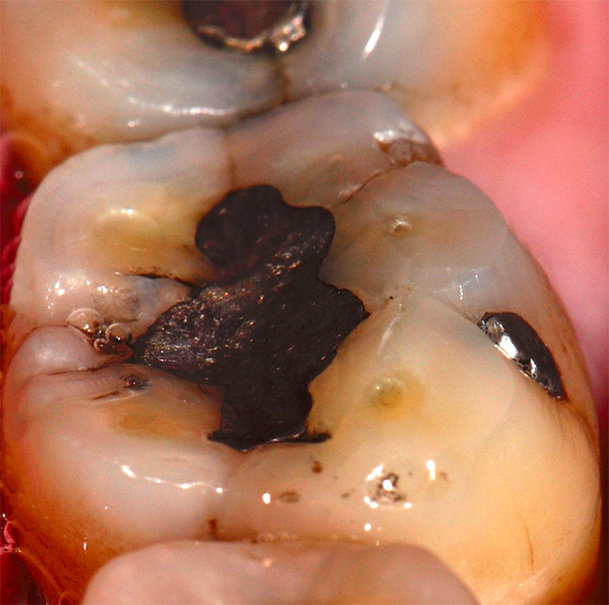

Aspect clinique et radiographique des lésions d’abrasion

Cliniquement, les lésions d’abrasion sont caractérisées par des facettes lisses, une absence de convexité et des bords à angles vifs. La flexibilité du ligament alvéolo-dentaire va entrainer un frottement au niveau des points de contact, qui peuvent se transformer en surfaces de contact (fig. 2c-d, 3 et 4b-c).

Radiographiquement, on observe une perte des cuspides et un aspect plan des faces occlusales (fig. 2a-b et 4a).